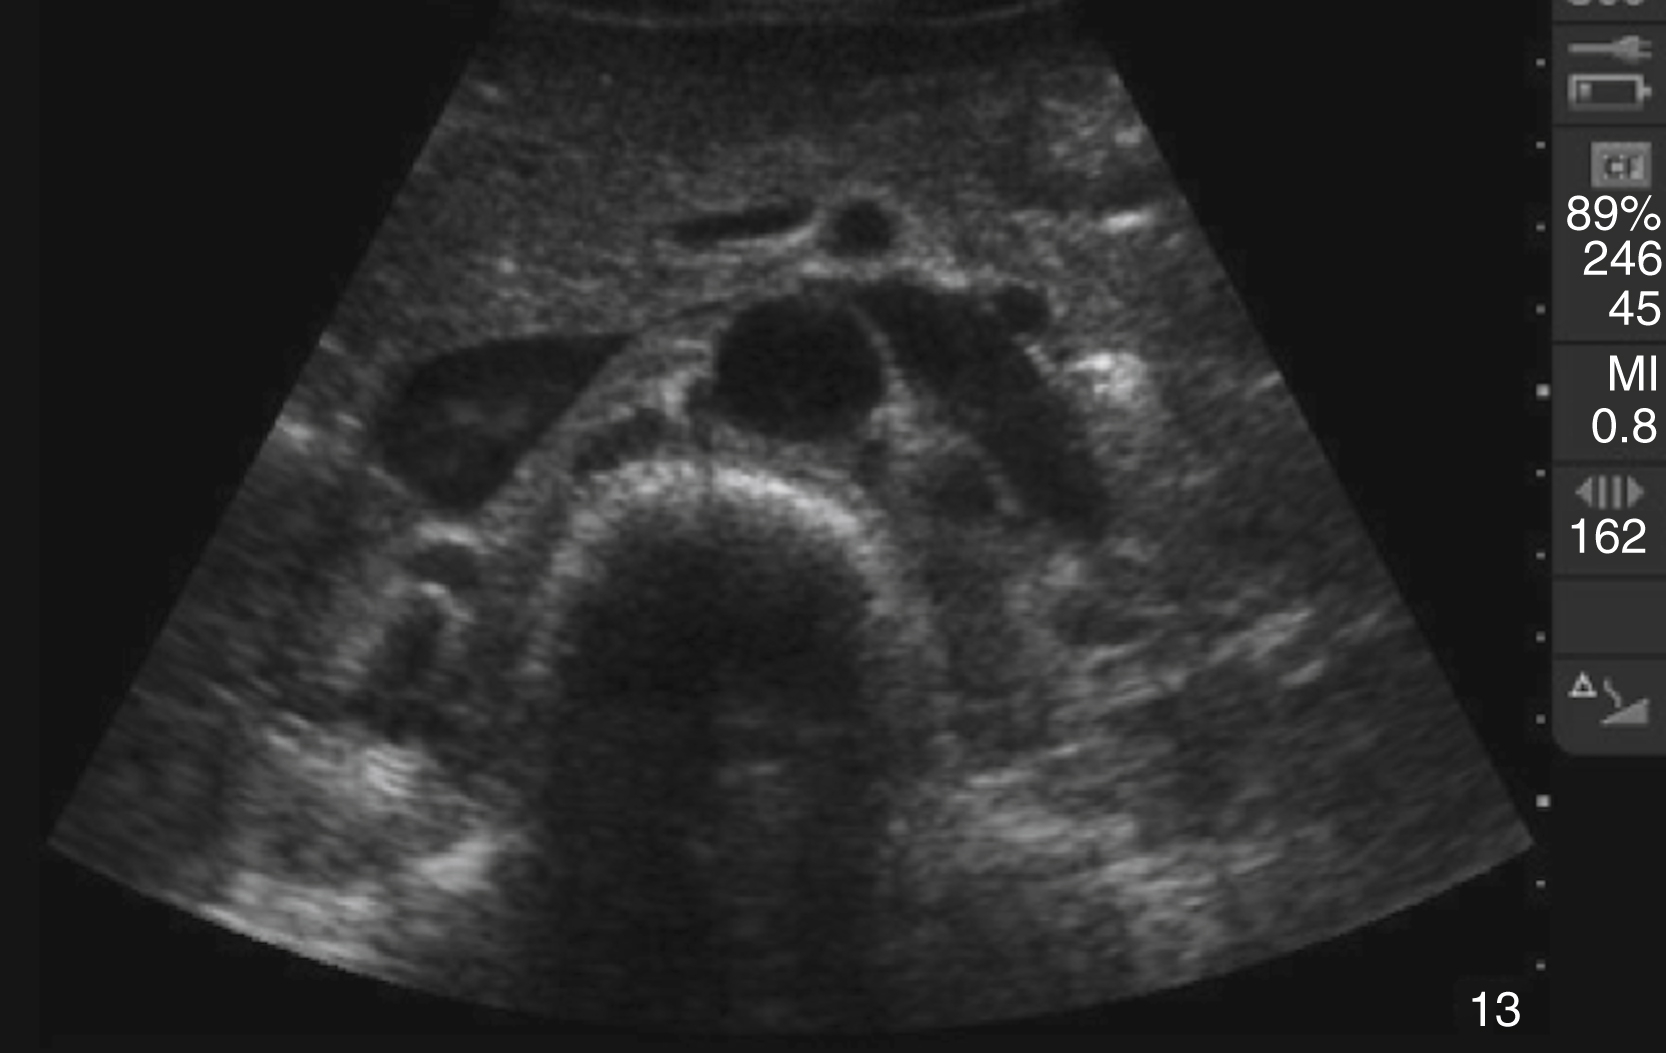

Pathology

An aortic diameter greater than 3 cm constitutes an abdominal aortic aneurysm, but risk of rupture increases with size and is rare with aneurysms smaller than 4.5 cm ( Fig. e3.8 and Video e3.7 ). A linear echogenic flap, anywhere across the lumen of the aorta, is suggestive of aortic dissection and may be associated with a different Doppler flow pattern on either side of the flap ( Fig. e3.9 and Video e3.8 ). The cardiac US examination may demonstrate an unexplained pericardial effusion, a dilated aortic root (>4 cm), aortic insufficiency, and/or a linear echogenic flap in the descending aorta.

Transverse view of a AAA with mural thrombus.

Aortic dissection flap visualized on longitudinal view of the aorta.